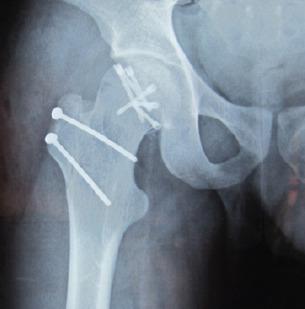

A 23-year-old male who sustained a high-energy trauma due to road traffic accident. He presented to ER with fracture of shaft femur, multi-ligament injury at the ipsilateral knee, fracture lower pole patella, ipsilateral fracture talus, and calcaneus along with comminuted fracture femoral head. He was managed by open reduction and internal fixation of the femoral head by safe surgical dislocation of the hip joint. Such injuries have been described rarely in the literature until now. The purpose of this report is to highlight the extreme rarity, possible mechanism involved, surgical management, and functional outcomes of such injuries.

Femoral head fracture without dislocation is a very rare entity, early diagnosis, especially in high-energy trauma scenarios to prevent the neglect and delay in the treatment which is the paramount importance of an excellent result in young patients.